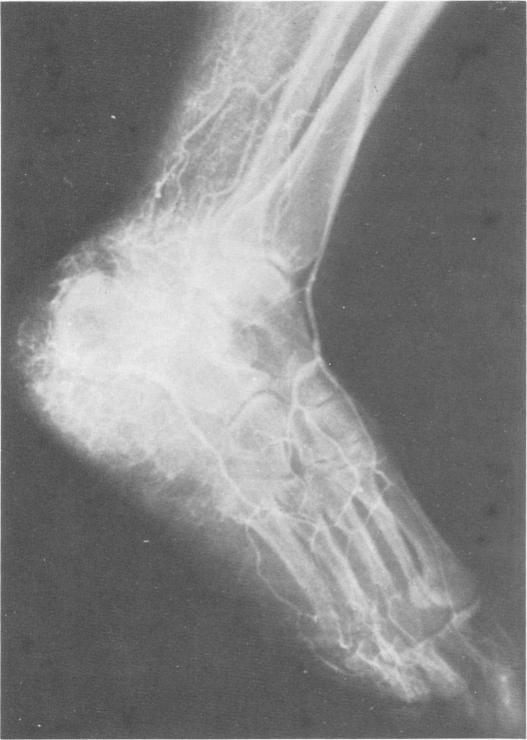

Nineteen patients with vascular deformities of the lower extremity were studied and were classified into three groups based on their clinical and angiographic findings. 1) The Klippel or Venous Dysplasia Group (n = 8) demonstrated: cutaneous nevi of metameric distribution, congenital varices (many of which were anomalous by phlebography), hypertrophy of bone and other tissues, but no evidence of arterial involvement by arteriography. 2) Congenital Arterio-Venous Fistulae Group (n = 7) showed: cutaneous angiomata, hypertrophy of bone and soft tissues, but arteriographic findings of single or multiple arterio-venous fistulae. 3) Scattered Angiomata Group (n = 4) had single or multiple angiomata involving the lower limb in particular. Arteriography was normal, while phlbography revealed venous abnormalities. Lymphography was performed on all patients. Six of 8 of the Klippel group demonstrated aplastic or hypoplastic lymphatics by lymphography. By contrast, all 7 of the patients in the Congenital Arterio-Venous Fistulae Group showed in their lymphographic findings-three of 4 of these patients had aplasia or hypoplasia. Fourteen of the 19 patients complained of painful swelling as a major symptom. Lymphatic fistulae and lymphoceles developed in several patients.Four patients underwent reduction operations for lymphedema. Lymphatic abnormalities as demonstrated by lymphography play a significant role in mixed vascular deformities of the lower extremities.